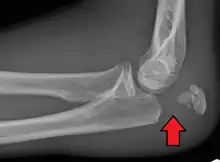

To assess an olecranon fracture, a careful skin exam is performed to ensure there is no open fracture. Then a complete neurological exam of the upper limb should be documented.[5][2] Frontal and lateral X-ray views of the elbow are typically done to investigate the possibility of an olecranon fracture.[1] A true lateral x-ray is essential to determine the fracture pattern, degree of displacement, comminution, and the degree of articular involvement.